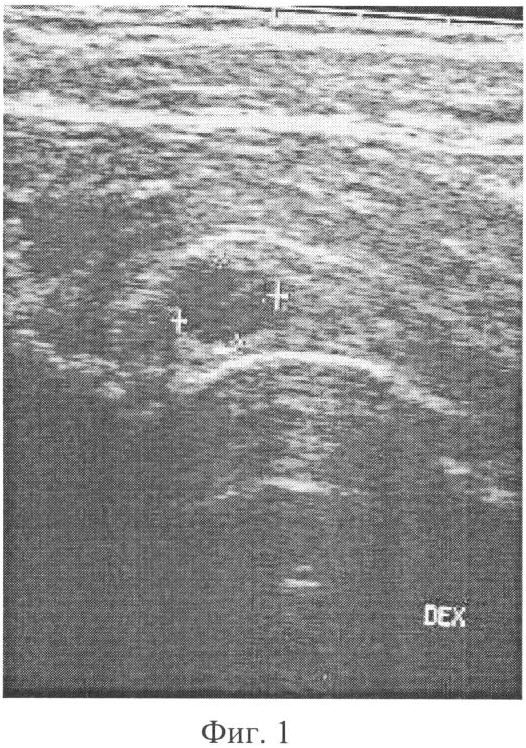

фиг.1 – представляет копию с сонограммы тазобедренного сустава пациента С. (до лечения) в прямой проекции с участком суставной губы (фиброзно-хрящевого кольца) вертлужной впадины по передне-наружной поверхности сустава, выявлена дегенеративная киста в области суставной губы, диагностирован остеоартроз I стадии.

В результате проведенного сонографического исследования тазобедренных суставов на аппарате «Sonoline» SL-450, в режиме реального времени, с использованием линейного датчика 7,5 МГц и усилением 36 dB в положении больного лежа на спине, при нейтральном положении тазобедренных суставов выявлено повышение плотности участка суставной губы (фиброзно-хрящевого кольца) вертлужной впадины по передне-наружной поверхности правого тазобедренного сустава – 26 у.е. и наличие в нем дегенеративной кисты. После диагностики раннего остеоартроза правого тазобедренного сустава пациенту проведен курс консервативного лечения. Для этого обезболивали кожу 0,5% раствором новокаина в количестве 4,0-5,0 мл и под контролем сонографии вводили иглу для инъекции в глубину до контакта с участком фиброзно-хрящевой губы по передней поверхности сустава. Затем через эту иглу вводили хондропротектор (афлутоп-2,0) в дегенеративную кисту. Введение хондропротектора осуществляли 3-5 раз через 2-3 дня.